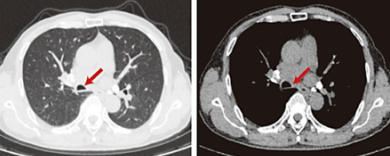

四个月后复查,CT显示钙化病灶完全消失,支气管镜下气道切口愈合良好,管腔通畅无狭窄、无黏液潴留,黏膜恢复正常。老陈彻底摆脱了呼吸困扰,回归正常生活,无任何不适与并发症。

图3:复查CT